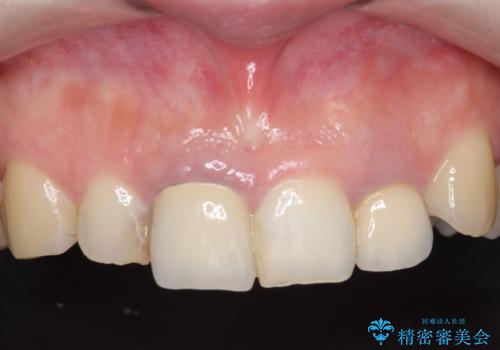

- 前歯の色や長さ、歯茎との隙間の金属が気になるのでセラミックで治療したいといらっしゃった方の症例です。

見た目改善のため、前歯4本をオールセラミッククラウン(スペシャル)で補綴しました。

右上1と左上2は再根管治療を行っております。

前歯の補綴ではオールセラミッククラウンを希望される患者様が多いですが、オールセラミッククラウンの中でも、エコノミー、スタンダード、スペシャル、エクセレントとランクがあります。

その中でも特に審美性が高いのがスペシャル、エクセレントです。スペシャル、エクセレントは口腔内写真をもとに熟練の技工士が、患者様の口腔内に合わせたオーダーメイドのクラウンを製作致します。